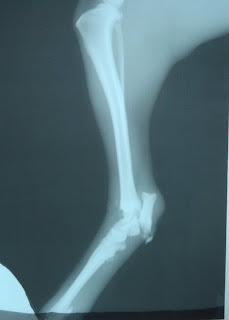

Here we would like to introduce our new cat, actually his x-ray : See

Well, you have to be a vet for the broken femur! The bone can not be saved, we believe Lucas was bitten by a dog and the leg is so inflamed that the bone is inflamed too, and that makes all the possibilities of success (if we would decide for an operation) is very low. So Lucas is now amputated ...

X-ray image of Airam s all broken hips: , and walking: